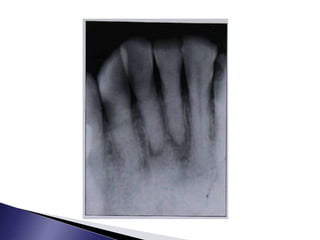

 The radiographic appearance of CM is partial or total obliteration of the

pulp canal space with a normal periodontal membrane space and intact

lamina dura.

 A thickening of the periodontal ligament space or periradicular

radiolucency may be observed with or without subjective symptoms .

 Complete radiographic obliteration of the root canal space, however, does

not necessarily mean the absence of the pulp or canal space; in the majority

of these cases there is a pulp canal space with pulpal tissue.